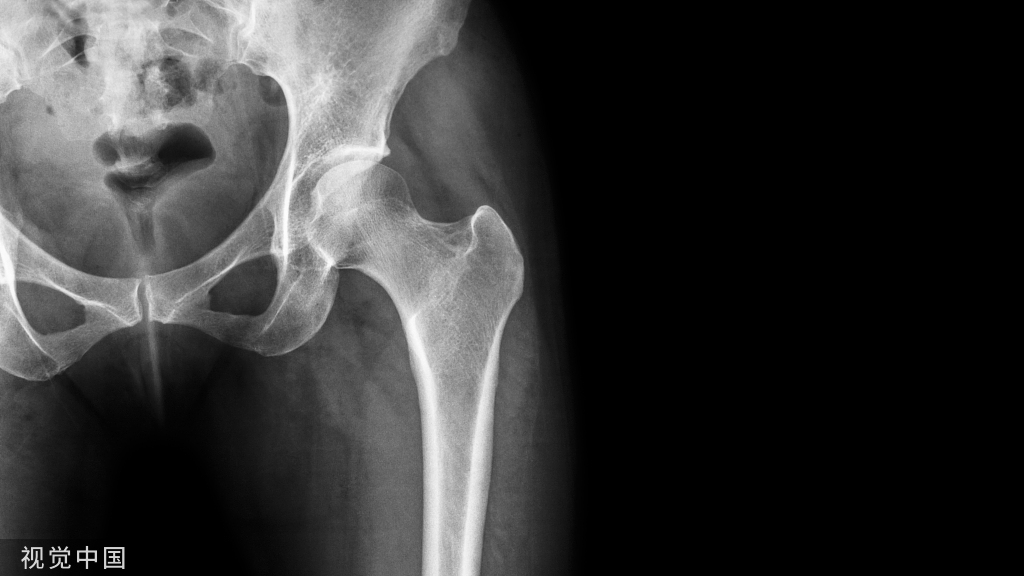

本研究旨在探讨桡骨远端和舟状骨合并骨折的特点,并确定手术和非手术治疗的结果差异。

由于舟状骨和桡骨远端骨折复位发生在相反的方向,这种骨折模式呈现出独特的围期和术后处理困难。桡骨远端骨折复位需要纵向牵引和伸展至屈曲运动,而舟状骨则需要压缩。在此过程中,桡骨远端复位操作理论上可以使舟状骨移位。在这些骨折的手术或非手术治疗过程中,相互竞争的力量对治疗提出了挑战。

方法:回顾性检索某一级创伤中心数据库15年间(2007-2022年)的成人桡骨远端和舟状骨合并骨折患者。我们对31例患者的损伤机制、骨折处理方法、桡骨远端骨折分类、舟状骨骨折分类、x线片舟状骨愈合时间、运动时间和其他人口统计学数据进行了回顾。对这些患者舟状骨骨折的手术治疗与保守治疗的结果进行了多变量统计分析。